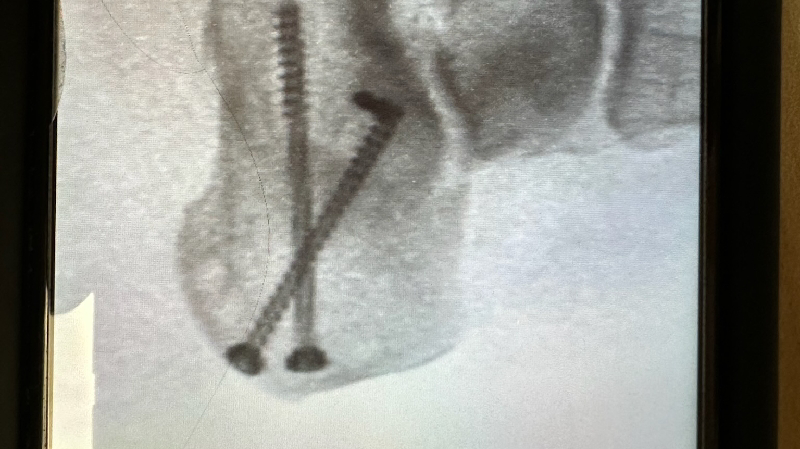

she's been working hard all her life but unfortunately a year and a half she had this unfortunately accident that she broke her heel bone in pieces she was ready to buy her dream house right before this accident happened now she spent all her savings in this situation and now she needs another surgery because the screws are coming out and she can potentially get the bone infected and high risk to get her foot amputate . . she cannot get social security and not disability because she worked with 1099 .. she needs help to keep up with rent and bills and she's terrified to get evicted most because she have two puppies that she needs to protect , and Plus she's been dealing with depression , she's in a good attitude and hope , from my heart thank you. Alma